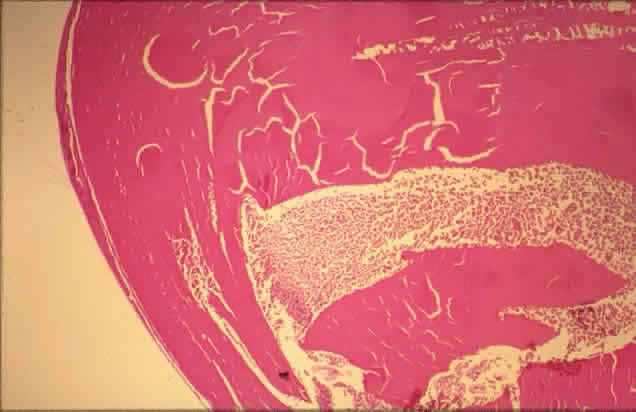

Histologically, new vessels develop between the retinal surface and the posterior surface of the formed vitreous (Fig. 12). With NVE, there is a demonstrable break through the internal limiting membrane (Fig. 13).20 Early-developing new vessels have lumina even at the proliferating tips.53 Active new vessels have endothelial cells and pericytes, with fenestrations. Morphologically, fenestrations are areas ranging from 40 to 80 nm in diameter where the cell membranes are focally fused, and are normal findings in capillaries outside of the retina and brain. They allow increased permeability and are responsible for the diffuse leakage of fluorescein seen from new vessels on angiography. Inactive or “ghost” new vessels are acellular, having lost both endothelium and pericytes.39 With time, fibrous tissue develops and accompanies the new vessels. The vessels themselves may leak and bleed into the vitreous, leading to visual loss.

Fig. 12. Neovascularization at the disc with fibrous proliferation. The fibrovascular membrane overlies the internal limiting membrane, which is wrinkled (arrows). The retinal detachment is artifactual. (PAS, × 19.5)

Fig. 13. Neovascularization away from the disc. The fibrous tissue has contracted, imparting a triangular shape to the membrane. Active new vessels are present throughout. The dark folds are artifactual. (H&E, × 31.25)

The fibrous tissue is contractile, and has been shown to contain actin filaments.54 Clinically, fibrous proliferation appears as whitish bands on the retinal surface, sometimes obscuring the neovascularization. With retinal elevation, retroretinal membranes also can form.

Traction can cause cystoid changes in the retina20 and venous loops,55 as well as retinal detachment (Color Fig. G). Extensive traction can cause macular heterotopia reminiscent of retinopathy of prematurity.56